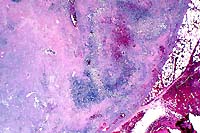

- Case 12-1. Oral mucosa with extensive ulceration (except

for lower right corner) & multifocal areas of liquefactive

necrosis surrounded by both suppurative and granulomatous inflammation.

20x

obj

- Case 12-1. Oral mucosa. Necrotic foci are centered

on an eosinophilic coagulum composed of necrotic cells and denatured

protein which forms picket fense-like radial projections (Splendore-Hoeppli

phenomenon). This material is surrounded by myriad eosinophils,

fewer neutrophils, and more distant accumulations of epithelioid

macrophages.

- Conference Note: This pedunculated to polypoid lesion

is covered by an extensively ulcerated stratified squamous nonkeratinizing

epithelium. Within the mass, there are multifocal to coalescing

nodular aggregates of eosinophils and macrophages that palisade

around degenerate, fragmented, and sometimes hyalinized, bundles

of collagen. Lymphocytes and plasma cells surround the eosinophilic

granulomatous nodules, and immature fibrous connective tissue

forms the peripheral boundaries of these inflammatory foci.